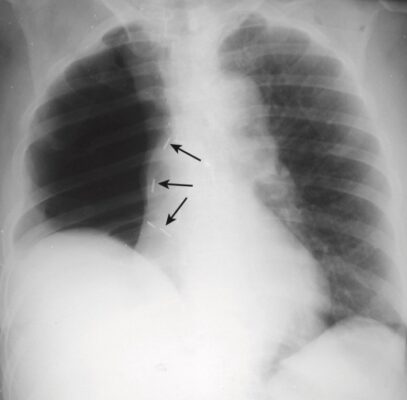

- Khi tích tụ đủ dịch màng phổi, tràn dịch lượng lớn sẽ “đẩy” các cấu trúc di động ra xa và có một sự dịch chuyển của tim và khí quản ra khỏi bên bị mờ (Hình 4).